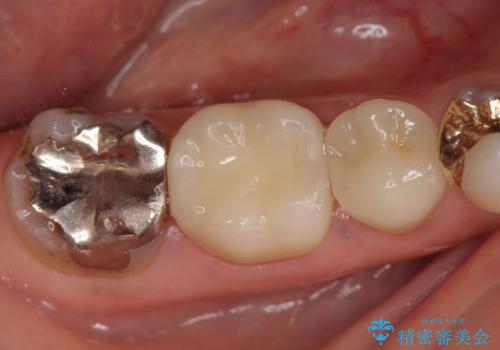

その後症状の消失を確認し、オールセラミッククラウンによる補綴を行いました。

今回用いたオールセラミッククラウンはジルコニアフレームという白い素材の上にセラミックを盛っているため、審美性が非常に高いのが特徴です。

また、ジルコニアは人工ダイヤモンドの材料にも使われているほど高い強度を持っており、そのためオールセラミッククラウンは審美性だけでなく、奥歯やブリッジの補綴も可能とするクラウンです。